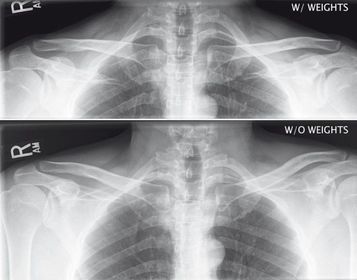

AP AC and SC Joints weight bearing and non weight bearing 72 SID 65-80 kVp 14x17 IR crosswise CR @ manubrium expose during suspended respiration *take first exposure without weights *8-10lb weights should be attached to wrists so the arms and clavicles will be relaxed for the 2nd projection

Bilateral AC Joints w/ weights